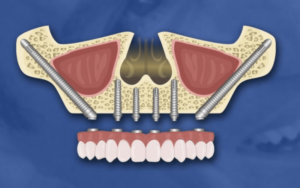

3. Zygomatic Implants in Charlotte, NC

Zygomatic implants are a specialized solution for individuals experiencing severe bone loss in the upper jaw, offering a stable foundation for a permanent upper bridge. Unlike traditional implants, these are considerably longer and are strategically anchored at an angle into the dense zygomatic bone, commonly referred to as the cheekbone.

Zygomatic implants are a highly effective and reliable dental solution offered in Charlotte, particularly for patients requiring upper jaw restorations. At Premier Dental, this advanced procedure is expertly performed by skilled surgeons, delivering numerous key advantages:

- Patients leave with fully functional, fixed teeth on the same day of the procedure.

- Zygomatic implants eliminate the need for upper dentures, providing a more natural and durable alternative.

- By anchoring into the cheekbone, they remove the need for bone grafting, simplifying the process.

- The treatment significantly shortens the timeline for future implants, bridges, or upper jaw restorations.

- Compared to traditional implant options, zygomatic implants are a more cost-effective solution.

- IV sedation ensures a comfortable, stress-free experience throughout the procedure.

- Recovery is fast, allowing most patients to return to daily activities shortly after surgery.

- Extractions and implant placement are usually completed in a single appointment, minimizing inconvenience.